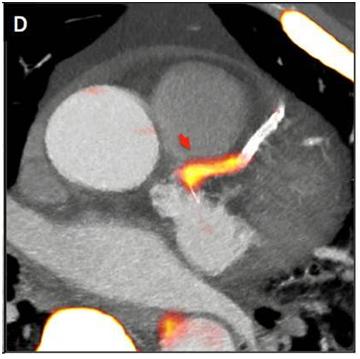

The plaque areas in the blood vessels were easily identifiable by using the Biograph mCT™ and tracers by lighting up as yellow on the resulting image.

The plaque areas in the blood vessels were easily identifiable by using the Biograph mCT. In the patients with angina, advanced notice that they had high-risk plaques and a heart attack may be imminent. These patients could then be targeted with aggressive therapy in order to try and avoid future events.